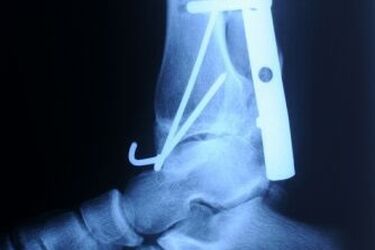

Fot: Publicum

Coraz częściej wszczepiane pacjentom metalowe implanty zastępują nowoczesne polimery. Prace badawcze nad polimerami bioresorbowalnymi rozpoczyna także białostocka spółka ChM.

Stosowanie tradycyjnych implantów ogranicza możliwość wykonywania niektórych badań, kluczowych dla oceny postępów leczenia lub do diagnostyki innych chorób tego samego pacjenta. Obecność implantów stalowych często uniemożliwia wykonanie rezonansu magnetycznego. Problem ten nie występuje w przypadku polimerów, które w medycynie są już powszechnie znane. W zależności od potrzeb, mogą być one bowiem w takich badaniach całkowicie niewidoczne lub lekko odróżniające się od otaczających je tkanek. Polimery bioresorbowalne ulegają z kolei stopniowemu i naturalnemu zanikowi w organizmie.